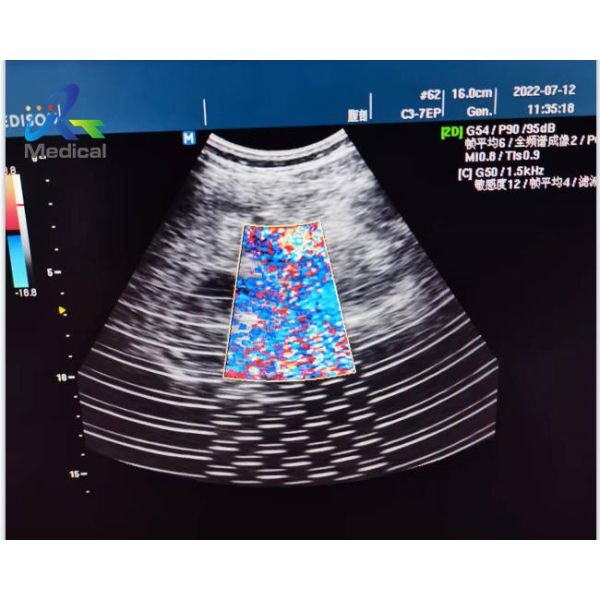

Medison X6v Ultrasonic Board Repair Solutions Image Interference

Maintenance process:

The two-dimensional images of the Madison X6 abdominal probe and

the superficial probe both have interference. After the blood flow

mode is turned on, the blood flow also has interference, and the

interference of the abdominal probe is the most serious.

Preliminary judgment is caused by environmental interference.

Maintenance results: After unplugging an external plug for charging the tram, it was found that the interference of the machine disappeared.